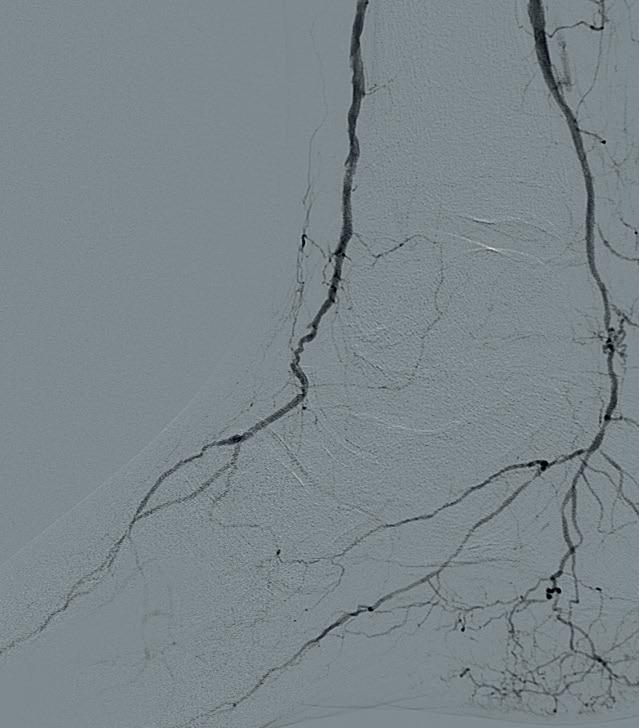

THE PATIENT IS A VIGOROUS 91year-old male with a past medical history of hypertension, hyperlipidaemia, and type II diabetes mellitus with resultant stage III chronic kidney disease. He is S/P coronary drug-eluting stent for symptomatic coronary artery disease and has a history of prostate cancer and prior right lower extremity deep vein thrombosis (DVT) complicated by postthrombotic syndrome with chronic edema. He developed ulcers on the right hallux as well as the second to fourth toes (Figure 1). A computed tomography angiography (CTA) of the lower extremity was notable for occlusion of all three infrapopliteal vessels. He was scheduled for a right below-the-knee amputation and came to see us for a second opinion. He was subsequently referred for angiography/intervention.

Ultrasound-guided access was obtained in the left common femoral artery and right lower extremity angiography confirmed nonobstructive inflow disease with tandem calcified 70 and 80% P1 as well as P2 extending into P3 disease. The anterior tibial

artery was noted to have a highgrade stenosis proximally with severe diffuse disease throughout its course, with essentially calcified occlusive disease distally with diffuse disease of the dorsalis pedis artery. The TP trunk was occluded proximally with complete occlusions of the TP trunk peroneal and posterior tibial vessels, with reconstitution of the posterior tibial artery above the ankle via geniculate collaterals. There was moderate diffuse disease of the plantar vessels as well (Figure 2a–c).

Figure 2a

Figure 2b Figure 2c